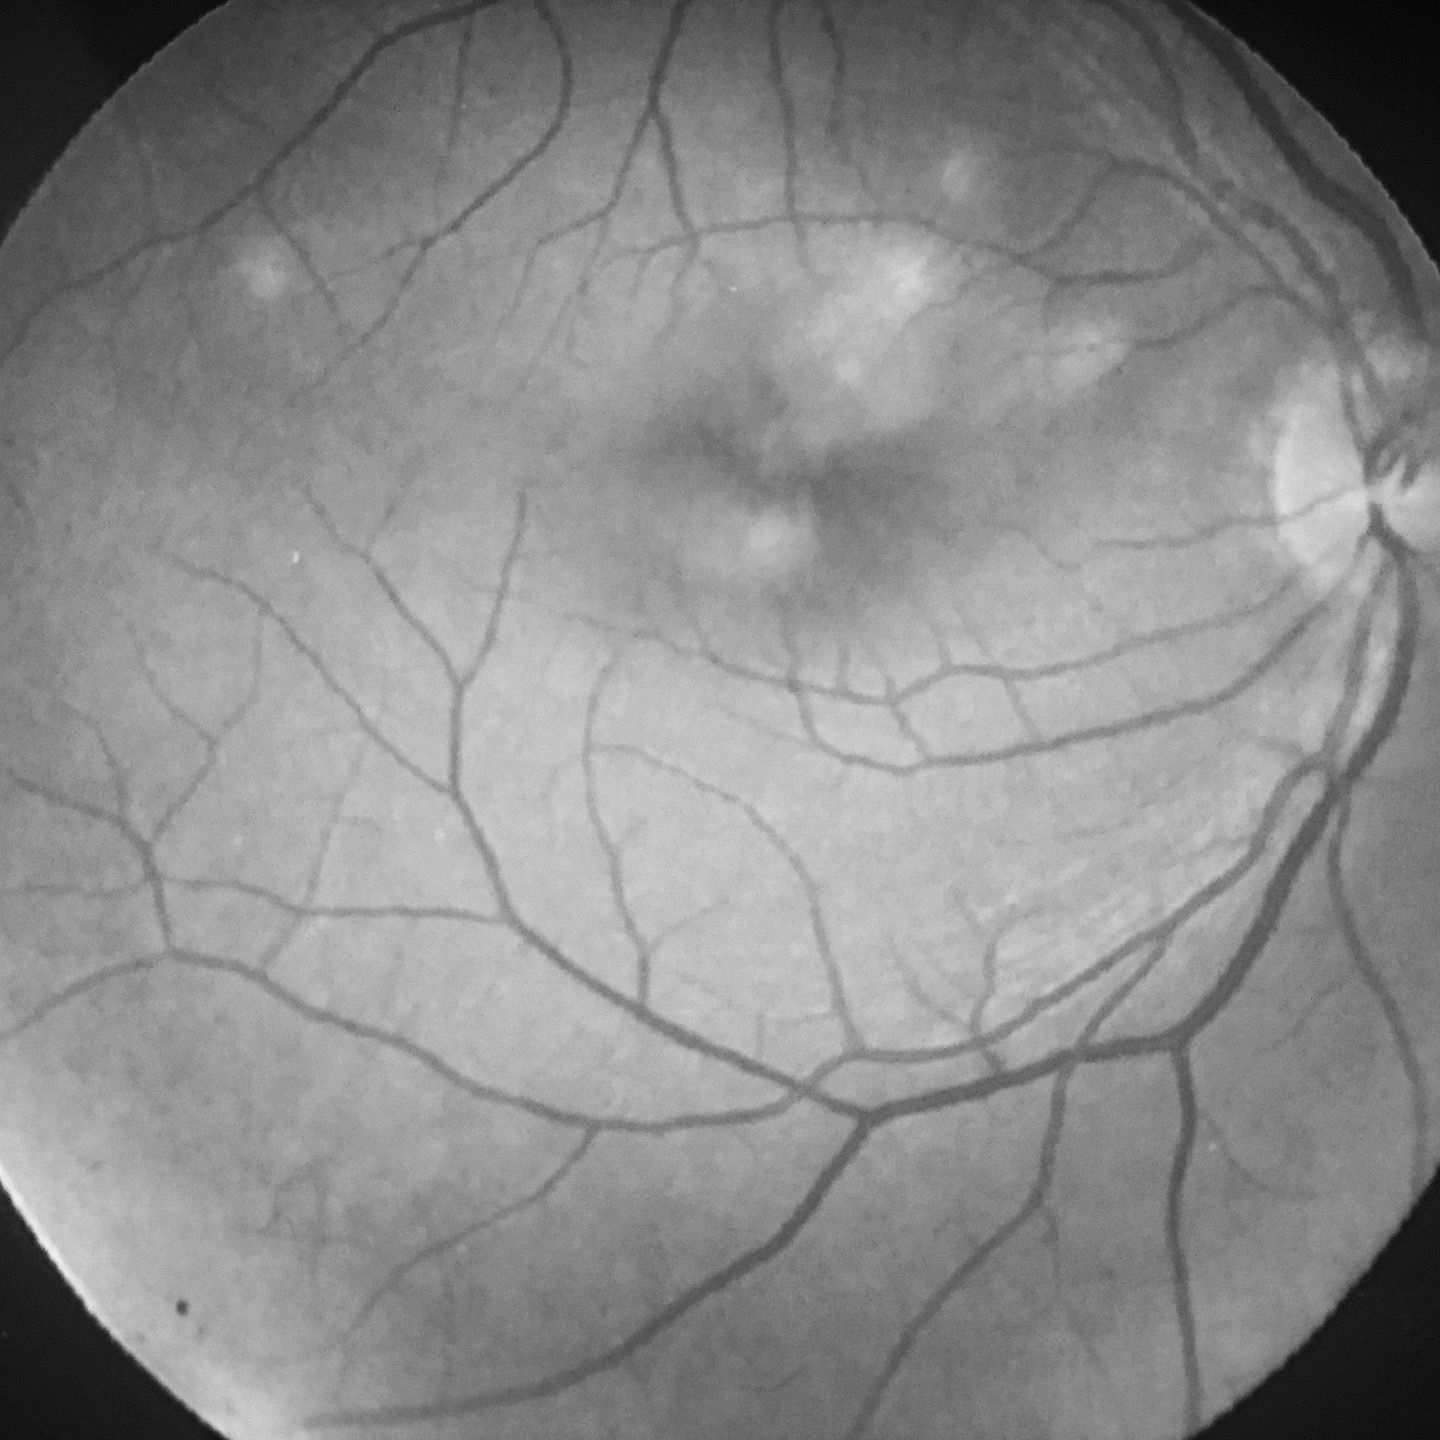

Fond d'oeil : corps flottants, myopie forte, trou/déchirure de rétine, myodesopsie

Pathologies rétiniennes : DMLA - dégénérescence maculaire liée à l'âge, diabète, myopie forte, occlusion veineuse...